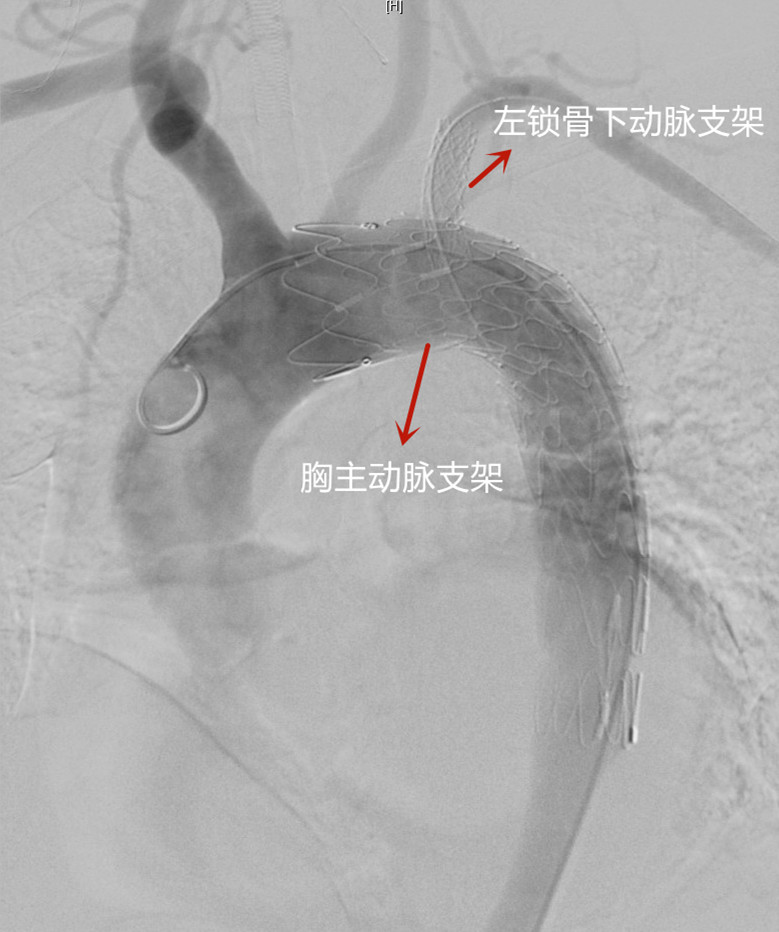

术中造影

胸主动脉支架、左锁骨下动脉支架植入后造影

术中在透视下,吴巍巍通过精确的定位,仔细沿血管壁送入胸主动脉支架,完全封堵锁骨下动脉及主动脉夹层破口。随后,吴巍巍经左侧肱动脉及锁骨下动脉,采用光纤在主动脉支架开孔并送入导丝,使用球囊扩张后精准植入支架,成功恢复胸主动脉与左锁骨下动脉的血液流通。历时一个半小时,血管外科成功为崔先生解除这颗“不定时炸弹”。术后崔先生恢复良好,精神头也不错,“谢谢大夫们!”崔先生激动地说。